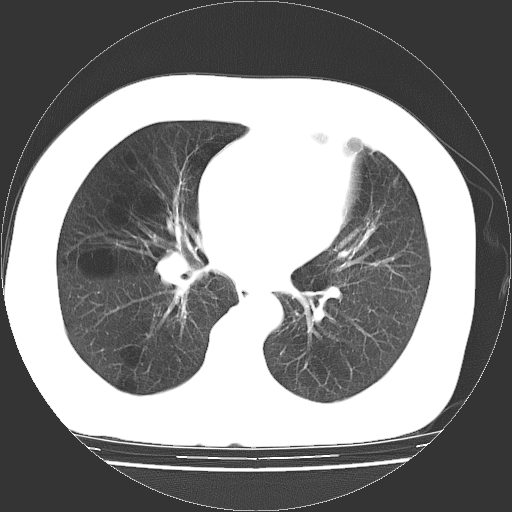

标题: CT13141:女,70岁,咳嗽、胸闷半个月。 [打印本页]

标题: CT13141:女,70岁,咳嗽、胸闷半个月。

女,70岁,咳嗽、胸闷半个月。纵隔窗未见异常,未上传。

小叶中心型肺气肿并多个肺大泡形成。

小叶中心性肺气肿及间隔旁肺气肿.(多与吸烟有关)

慢性支气管炎合并小叶中心性肺气肿及间隔旁肺气肿.(多与吸烟有关)。